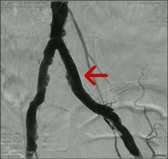

可怕的LEADDP 糖尿病下肢血管病变(LEADDP)可致患者肢体麻木、疼痛,间歇性跛行,乃至坏疽(糖尿病足),截肢率高达40 %以上。LEADDP是糖尿病致残、致死的主要原因,糖尿病患者因LEADDP造成的截肢,要比非糖尿病患者高5到10倍以上。先进的DSA + 微创介入 1、选择性血管造影(DSA)是LEADDP诊断的金标准。 2、微创介入治疗优点: 创伤小,仅有一2-3 mm的穿刺创口 成功率高:目前其成功率达85-90 % 保肢率高:术后病人截肢率可从40 %降为4 %左右 早发现早治疗:越早治疗效果越好.独创的微创介入 + HBO + bFGF综合治疗途径 1、DSA + 微创介入 2、高压氧(HBO)物理疗法:大型空气加压舱,治疗压力0.2 MPa,面罩吸纯氧30 min 3、基于重组成纤维细胞生长因子(bFGF)局部换药.